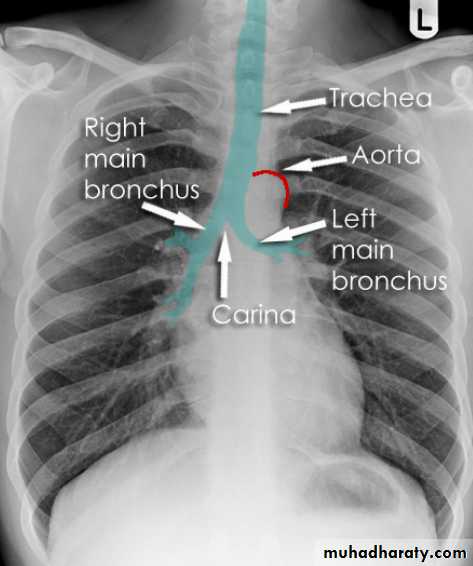

Hilar structuresThe hila (lung roots) are complicated structures mainly consisting of the major bronchi and the pulmonary veins and arteries. These structures pass through the narrow hila on each side and then branch as they widen out into the lungs. The hila are not symmetrical but contain the same basic structures on each side.

Each hilum contains major bronchi and pulmonary vessels

There are also lymph nodes on each side(not visible unless abnormal)

The left hilum is often higher than the right

Both hila should be of similar size and density. If either hilum is bigger and more dense, this is a good indication that there is an abnormality.